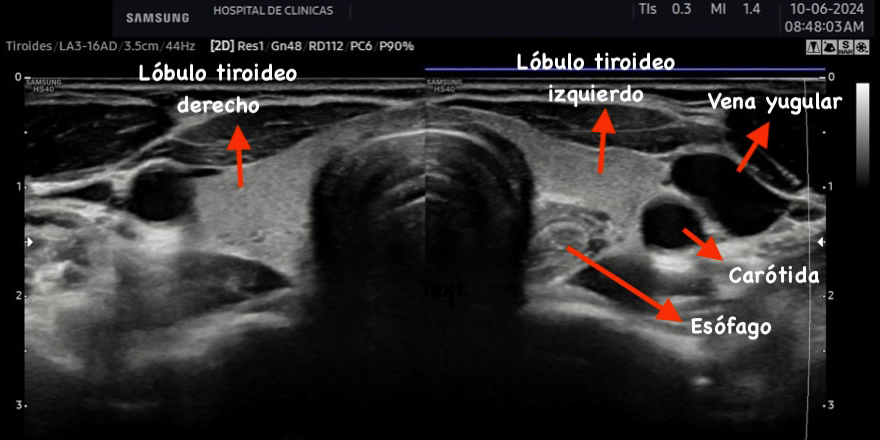

La tiroides de un adulto tiene un tamaño variable de aproximadamente 13 a 18 mm de ancho o transversal (T), 16 a 18 mm de profundidad o anteroposterior (AP) y 45 a 60 mm de largo o longitud (L), el istmo mide entre 2 a 6 mm de profundidad (AP). El volumen del lóbulo se calcula mediante la fórmula V (ml) = 0,479 × AP × T × L (cm). El número 0,479 o 0,524 en la fórmula es el factor de corrección para determinar el volumen de estructuras de una forma elipsoide, existen varias constantes y puede utilizarse cualquiera de ellas. El volumen de la tiroides es la suma de los volúmenes de ambos lóbulos. El volumen del istmo por ser pequeño, en general inferior a 10 mm no está incluido2. El volumen de una tiroides normal tanto en adultos como en niños es fuente de debate. La Organización Mundial de la Salud sugiere un volumen normal en hombres de 7,7 a 25 cm3 y en mujeres de 4,4 a 18 cm3(2). Depende de la edad y el área de superficie corporal de cada individuo2.

La ecogenicidad es media o alta cuando se compara respecto a los músculos pre tiroideos, tiene aspecto granular fino similar a las glándulas salivales y es isoecoica respecto a estas últimas. Cuanto más coloide y menos células haya en la glándula se produce mayor reflexión del sonido, por lo tanto, mayor ecogenicidad con respecto a los músculos pre tiroideos y demás tejidos como se observa en la figura 26.

La eco estructura es homogénea, los márgenes son regulares y presenta una cápsula ecogénica, su vascularización es escasa. El rango de referencia para una tiroides normal es de entre cinco y diez vasos visibles dentro de la exploración de cada lóbulo valorado con Doppler color2. Se ha descripto que hasta un 50% de los individuos presentan lóbulo piramidal (Figura 3a y 3b). Este sector, en general, es similar en ecogenicidad, homogeneidad y vascularización al istmo y los lóbulos. En la superficie posterior de los lóbulos tiroideos, especialmente en el segmento inferior, puede visualizarse el tubérculo de Zuckerkandl, un ejemplo de este se puede observar en la figura 4a y 4b. Este es un tabique hiperecogénico fibroso que a menudo genera sombra posterior. Se forma por la extensión del tejido tiroideo de las áreas laterales de los lóbulos hacia el sector posterior, y a menudo exhibe una disminución de la ecogenicidad detrás del mismo. Este proceso puede imitar una lesión tiroidea o paratiroidea y causar dificultades en la interpretación2.

Figura 2: Corte transversal de la tiroides normal, se señalan con las

flechas distintas estructuras.